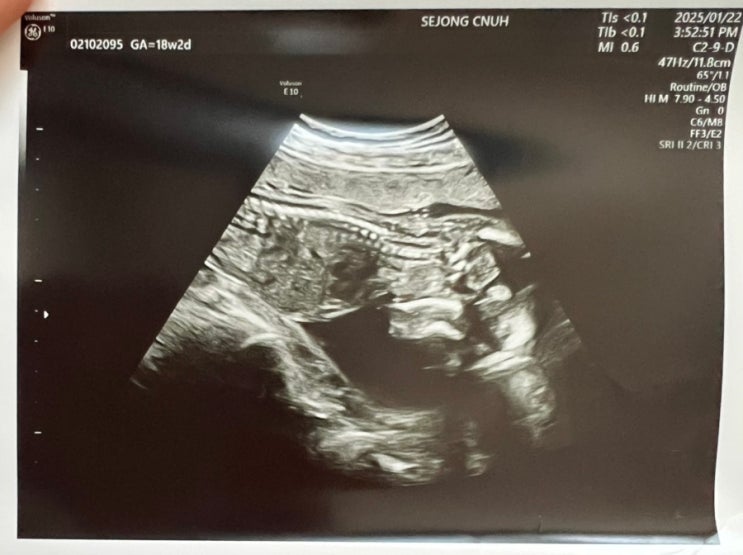

[임신 18주 2일] 아기 초음파 & 기형아검사(쿼드검사)결과

안녕하세요. 토디맘입니다:D 18주에는 보통 산부인과 안 가시는 주수이긴 하지만 13주에 예방맥을 했던터...